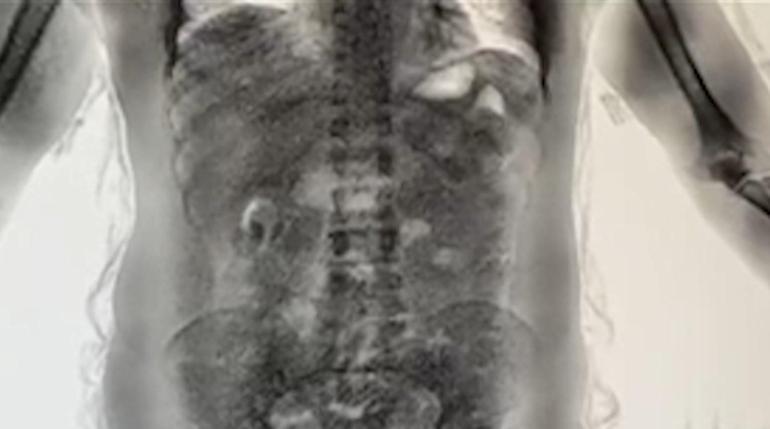

KURYELER RÖNTGENLE TESPİT EDİLİYOR

DHA muhabirine yapılan değerlendirmede, riskli ülkelerden gelen yolcuların ekipler tarafından yakın takibe alındığı belirtildi. Uçağın kapısından itibaren terminal içerisinde riskli görülen yolcular, ekipler ve güvenlik kameraları tarafından anbean izleniyor. Şüpheli kişiler gümrük ekiplerince durdurulduktan sonra ilk olarak bagajları aranıyor. Yapılan aramalarda herhangi bir bulguya rastlanmaması halinde, hal ve tavırlarından şüphelenilen yolcular 'yutucu tespit cihazlarının' bulunduğu bölüme götürülüyor. Burada yapılan röntgen incelemesinde, şüphelilerin mide ve bağırsaklarında uyuşturucu madde bulunduğu tespit ediliyor.